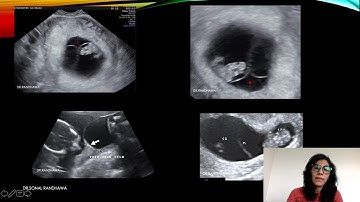

CASE 546 Fused two placenta with lambda sign ,twin peak sign